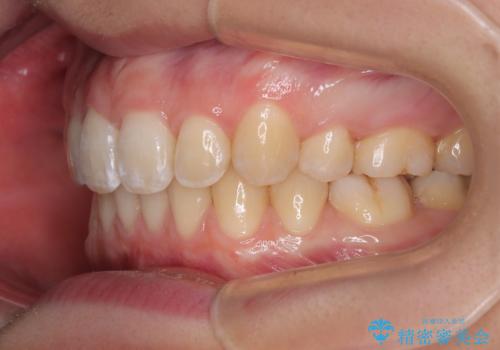

上下の抜歯位置を変えることで、左右ともに理想的な咬み合わせを達成することができました。

横顔の印象はほとんど変わらないものの、唇を閉じたときに前に出ていた下唇が、治療後には少し下がった状態に仕上げることができました。